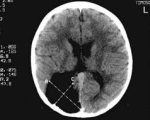

• Компьютерная томография головного мозга. Компьютерная томография проводится детям старшего возраста, взрослым. Новорожденным и детям раннего возраста проводится в исключительных случаях по назначению врача. По изображениям можно обнаружить полое объемное новообразование, не имеющее твердого компонента и не поглощающее рентгеноконтрастные вещества. Одна особенность - отсутствие масс-эффекта даже при большой порэнцефалической кисте.